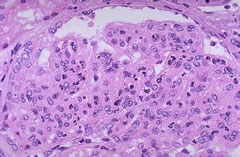

子宫颈鳞状上皮内病变(SIL)

疾病介绍:是与子宫颈浸润癌密切相关的一组子宫颈病变,常发生于25-35岁如女。大部分低级别鳞状上皮内病变LSIL)可自然消退,但高级别鳞状上皮内病变(HSIL)具有癌…【详细】